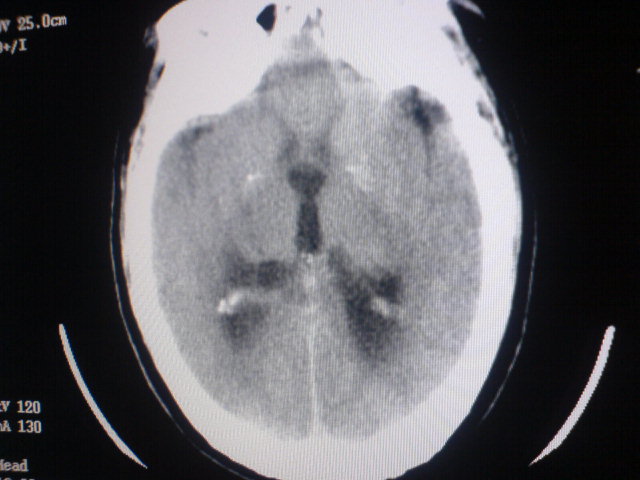

标题: CT17158:抽搐 [打印本页]

标题: CT17158:抽搐

脑积水,原因待查。

资料太少,大胆推测:脑干病变,中央孔受阻致脑脊液回流障碍脑积水。

考虑1小脑吲占位,2四脑室室管膜瘤

中线松果体区肿瘤?做增强会有帮助鉴别